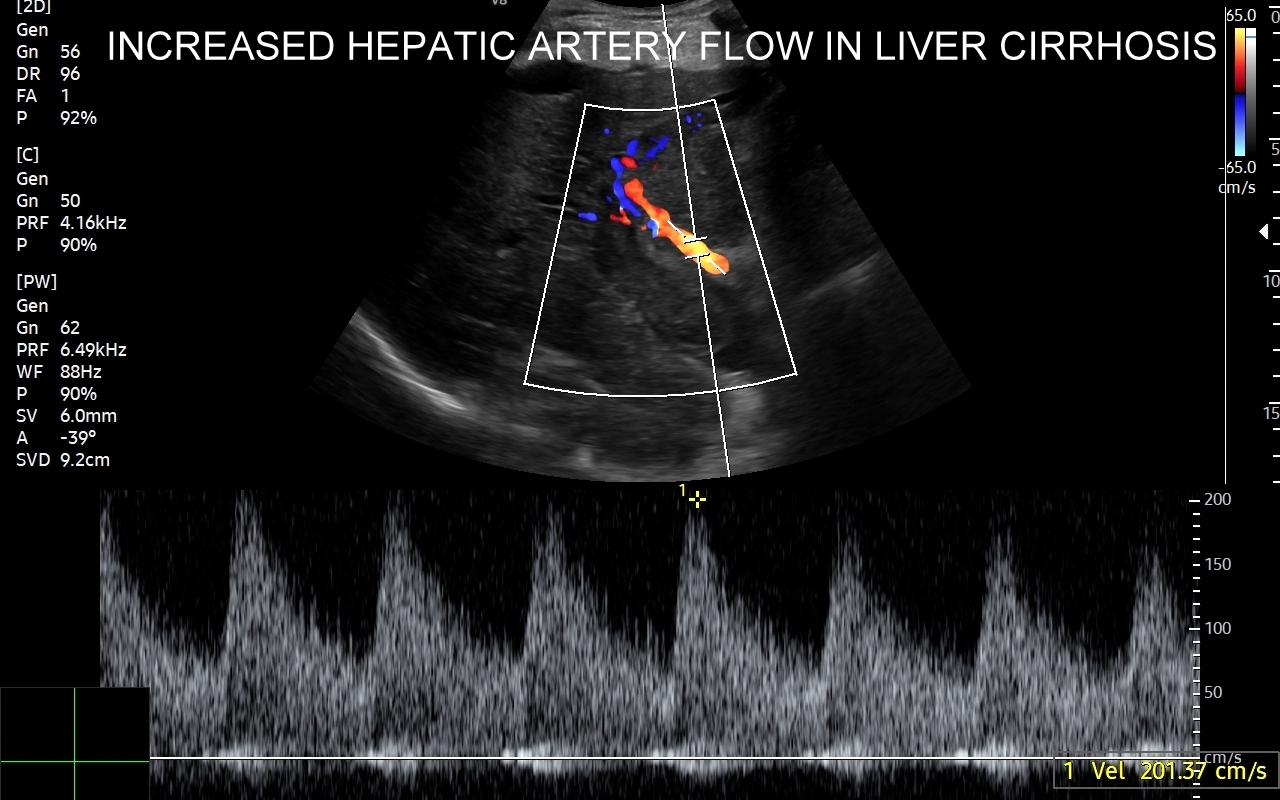

Wątroba posiada unaczynienie różnego typu, a każde o swojej indywidualnej charakterystyce. Są to unaczynienie tętnicze, unaczynienie wrotne (żyła wrotna i jej dopływy z narządów jamy brzusznej), odpływ żylny poprzez żyły wątrobowe. W USG Doppler przepływów wątrobowych bada się każdy z tych układów.

Badanie USG Doppler układu wrotnego wątroby łącznie ze standardową oceną morfologii wątroby i śledziony wykonywane jest najczęściej w ramach diagnostyki nadciśnienia wrotnego, czyli podwyższonego ciśnienia krwi w żyle wrotnej, które może być przyczyną zagrażających życiu żylaków przełyku. Badanie dopplerowskie wątroby uzupełnia również diagnostykę marskości wątroby oraz służy wykrywaniu takich patologii jak zakrzepica w żyle wrotnej i jej dopływach, zakrzepica w żyłach wątrobowych, czy rozprzestrzeniające się nowotwory w naczyniach wątroby.